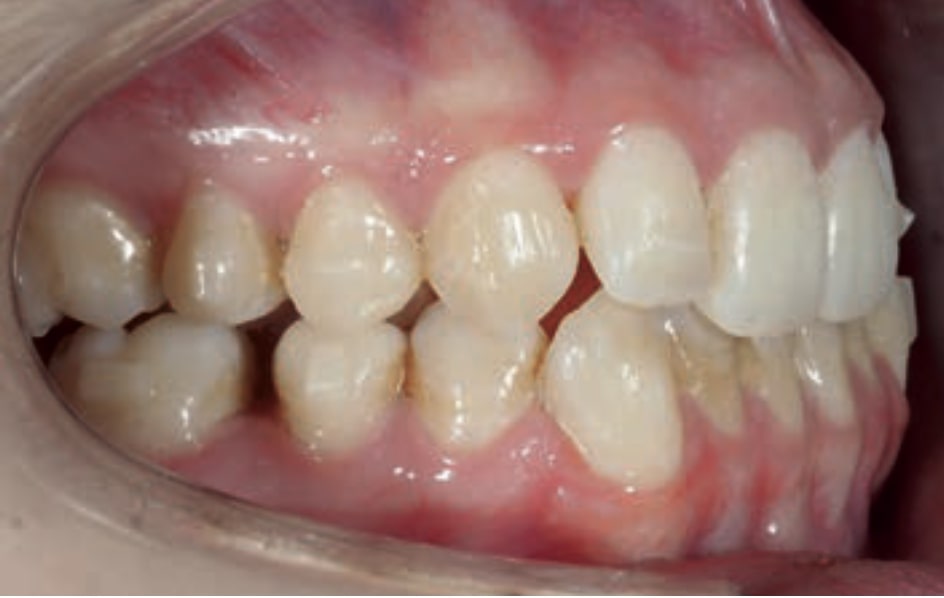

Chief complaint: The patient, a 19-year-old woman, was evaluated to undergo orthodontic treatment using the Angel Aligner Pro system. She presents with a skeletal Class III, mesofacial, with a dental Class III malocclusion and a 2 mm deviation of the lower midline to the left. Teeth 33 and 43 are out of the arch and cortical bone, with a crossbite issue on tooth 33. Fortunately, no functional issues affecting swallowing or breathing have been detected. The patient’s motivation for starting treatment was a general review of her dental and aesthetic health. The soft tissue analysis reveals mandibular protrusion that influences her facial profile. This diagnosis highlights the need for a comprehensive approach to address dental and skeletal misalignments, improving both the patient’s functionality and facial aesthetics.

Initial Photos and datas

Clinical examination and diagnosis

- Patient Age: 19 years old

- Skeletal class III

- Dental Class III, 2 mm deviation of the lower midline to the left. 33 and 43 out of the arch and the cortical bone.

- Crossbite of 33.

- No functional issues

- Patient Motivation: General Review

- Soft Tissue Analysis: Jaw protrusion